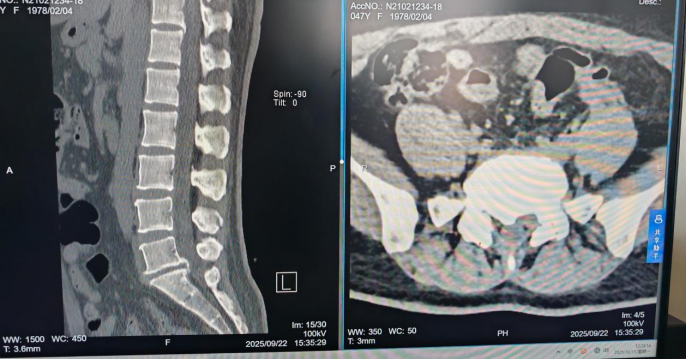

术前腰椎CT图像